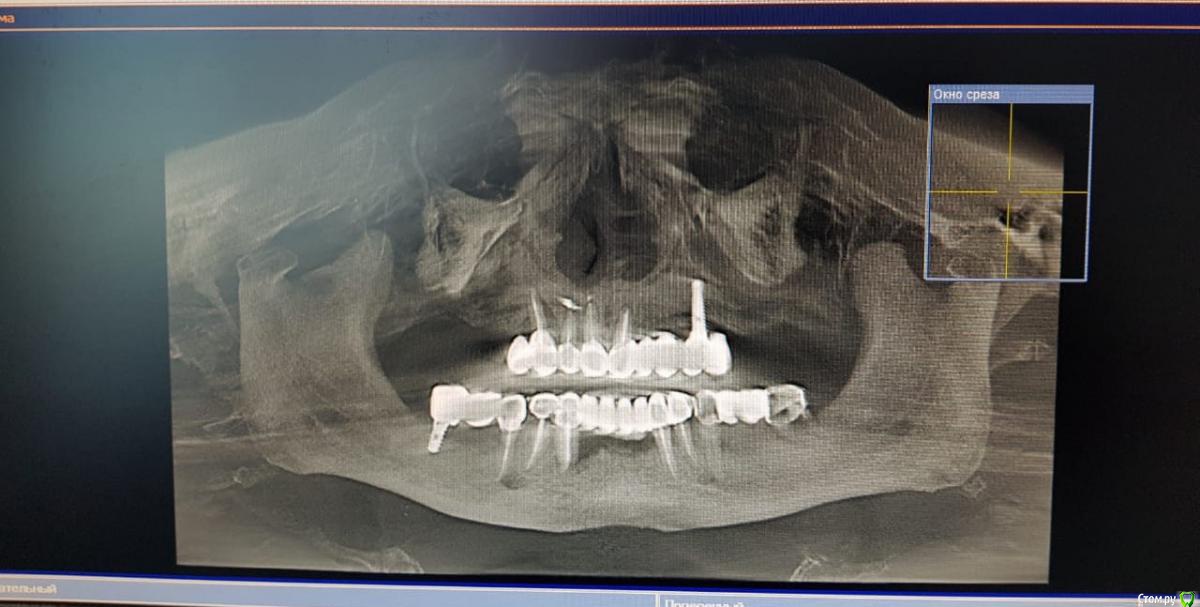

Sunshine Опубликовано 14 марта, 2019 Поделиться Опубликовано 14 марта, 2019 Уважаемые, врачи!Моему отцу 2,5 года назад установили импланты (в другом регионе), и сделали мост, "зацепившись" за живой зуб и имплант...Его ничего не беспокоило до недавнего времени. Теперь вся эта конструкция начала ходить ходуном ... приносит ему боль, естественно полноценно кушать не может.Обратившись в стоматологию по новому месту жительства, стоматологи сообщили, что так делать нельзя ни при каких обстоятельствах, и что надо все снимать, оставшиеся зубы удалять, ждать пока рассосется образовавшаяся киста в районе существующего импланта, и устанавливать новые импланты. Соответственно, вопрос. Так как отец в пенсионном возрасте, то крайне боится вообще остаться без зубов, для него это трагедия. Какие существуют варианты развития событий в нашей ситуации в "щадящем" режиме, но чтобы было все грамотно и четко сделано, дабы больше не возвращаться к вопросу зубов на верхнем ряду. p.s врач который устанавливал данную конструкцию сказал чтоб приезжали-он все поправит, но я его уже не отпускаю, потому что думаю это снова на пару лет...а дальше только хуже... Ссылка на комментарий

kramer Опубликовано 14 марта, 2019 Поделиться Опубликовано 14 марта, 2019 Если нужен несъемный протез, тогда надо удалять все зубы и прежний имплантат, одномоментно ставить 4-6-8 имплантатов (надо более детально изучать случай), временный несъмный протез в день операции или через несколько дней. Ссылка на комментарий

kramer Опубликовано 14 марта, 2019 Поделиться Опубликовано 14 марта, 2019 а что возможно сделать, не прибегая к удалению оставшихся зубов? Имеет ли смысл оставлять их? Какие последствия? Зубы верхней челюсти несостоятельны, сохранить нельзя Если на время удаления всей конструкции ставить съемный протез(это я так понимаю снимаются на ночь и в стаканчик? )), то это же только на то время пока не приживутся новые имплантаты? (примерно 3-6 месяцев) Временный протез несъемный, прикручивается в день операции или через несколько дней (при условии, что первичная стабильность имплантатов хорошая. Если нет, тогда как по сценарию, который вы написали) и что с кистой? Удаляется вместе с имплантатом Ссылка на комментарий